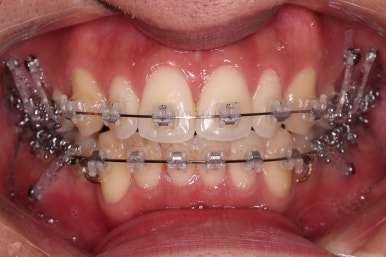

치료시작 6개월 정도 시점의 모습인데, 이정도만 해도 교정이 잘 된 듯 하지만 이제 시작입니다.

얼굴 모습 개선을 위해 해야 될 점들이 많습니다.

교합이나 가지런한 느낌 매우 좋아졌고요.

특히 옆 라인에서도 둥글었던 윗입술도 오목한 곡선이 생기면서 돌출감이 좋아졌고 턱끝의 윤곽도 생기면서 무턱 느낌도 좋아졌습니다.